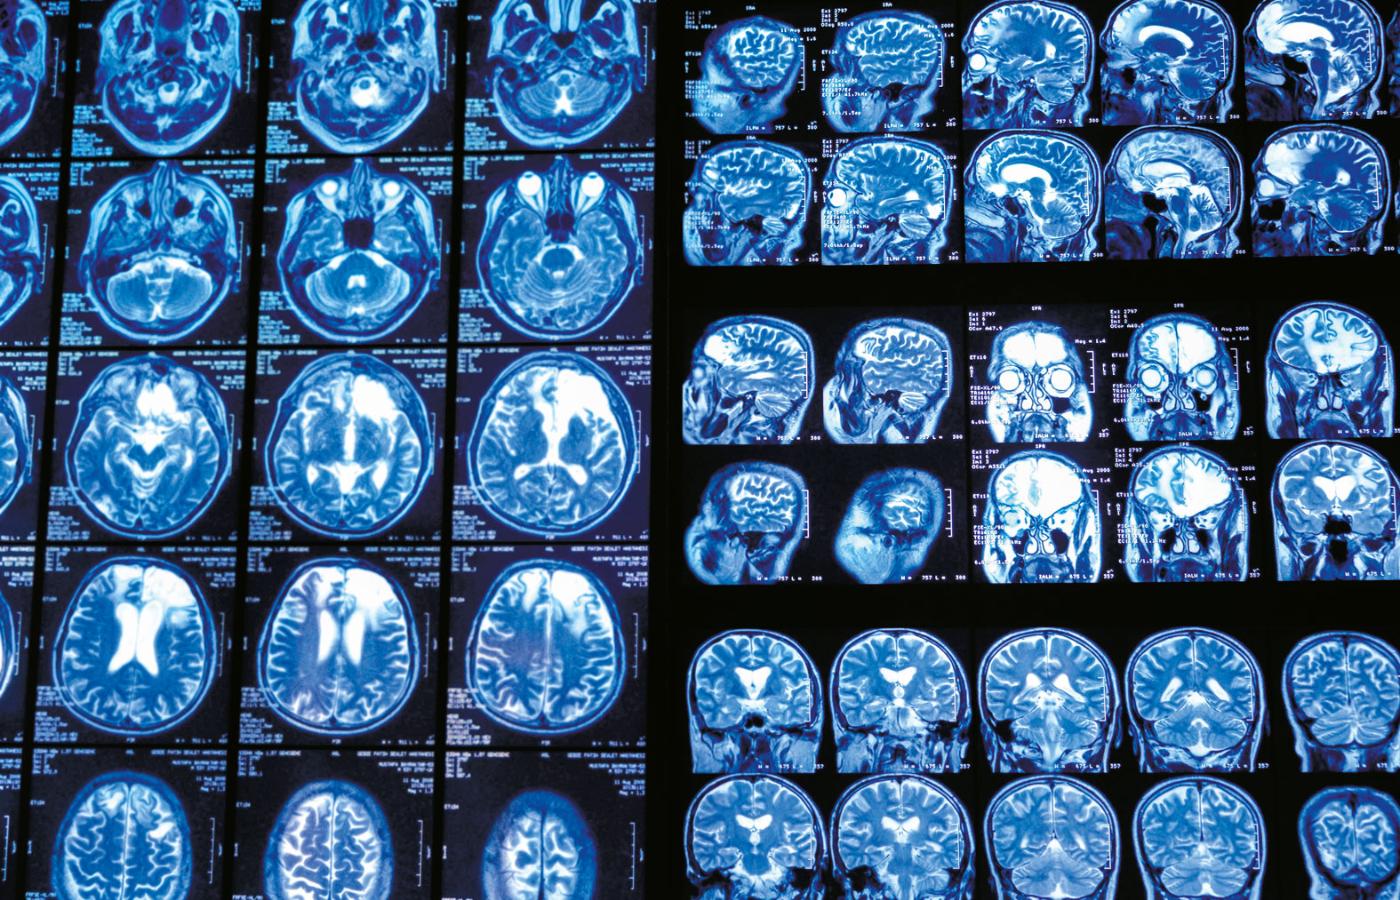

Z czego wynikają te niepokojące wzrosty zachorowalności? Częściowo na pewno z lepszych narzędzi do wykrywania chorób. Lekarze dysponują diagnostyką obrazową, np. rezonansem magnetycznym (MRI) i tomografią komputerową (CT).